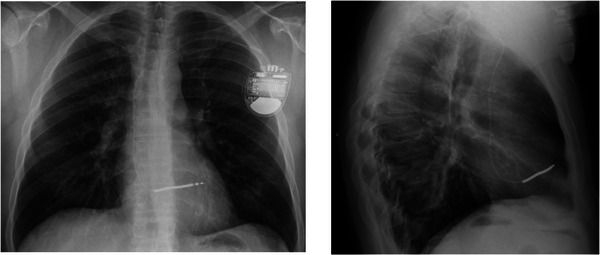

Introduction: Right bundle branch block (RBBB) following cardiac device extraction has not been previously reported but may have catastrophic consequences.

Methods and results: We present two cases of young male patients who developed RBBB following the extraction of single chamber TV ICD systems where the coil was adherent close to the superior tricuspid valve annulus. Both patients had a subcutaneous ICD (SICD) implanted but suffered an inappropriate shock due to T-wave oversensing, requiring very early SICD removal for one patient.

Conclusion: The development of RBBB following the extraction of a TV ICD is a previously unreported complication and may cause significant sensing problems if an SICD is implanted subsequently. Placement of the ICD lead tip in the right ventricular outflow tract or high on the intraventricular septum may predispose to this complication.